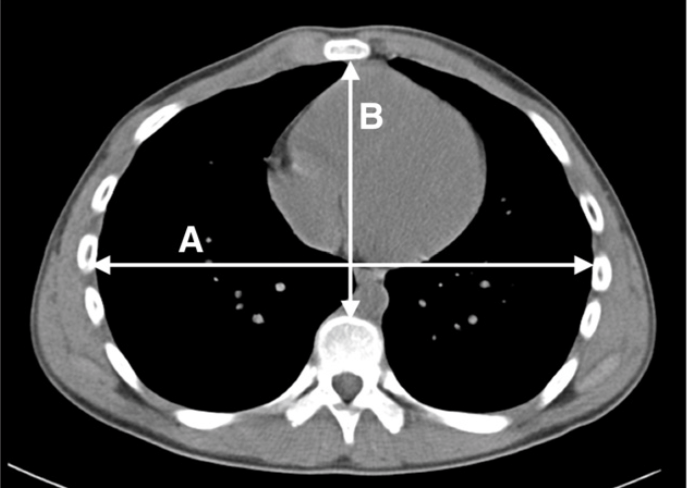

Dimensions used for Haller index calculation. | Download Scientific Diagram

The haller index is calculated by dividing the width of the rib cage by the distance from the sternum to the spine. Transverse width of chest cavity/narrowest sternovertebral depth. A ct scan of a 14 year old male with severe pectus excavatum. An index greater than 3.25 is considered severe enough to warrant surgical correction. Lietman,1 is a mathematical relationship that exists in a human chest. Dies genügte für den ersten platz im moderat steigenden index der mittelgroßen werte mdax. The haller index, created in 1987 by dr.